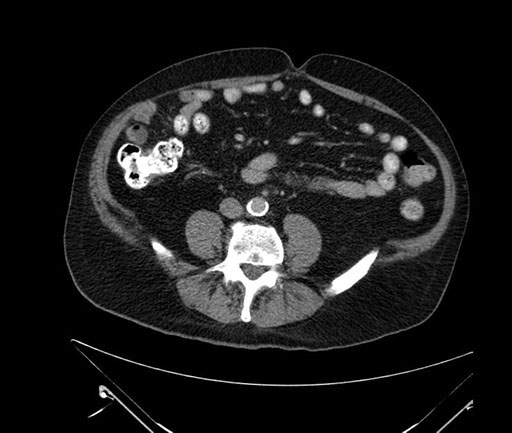

Imaging Analysis

Look through the patient's CT scan to identify any areas of concern for the necessary procedure.

Based on your CT findings, which issue(s) would give reason for "planned slowing down moment(s)" in this case?